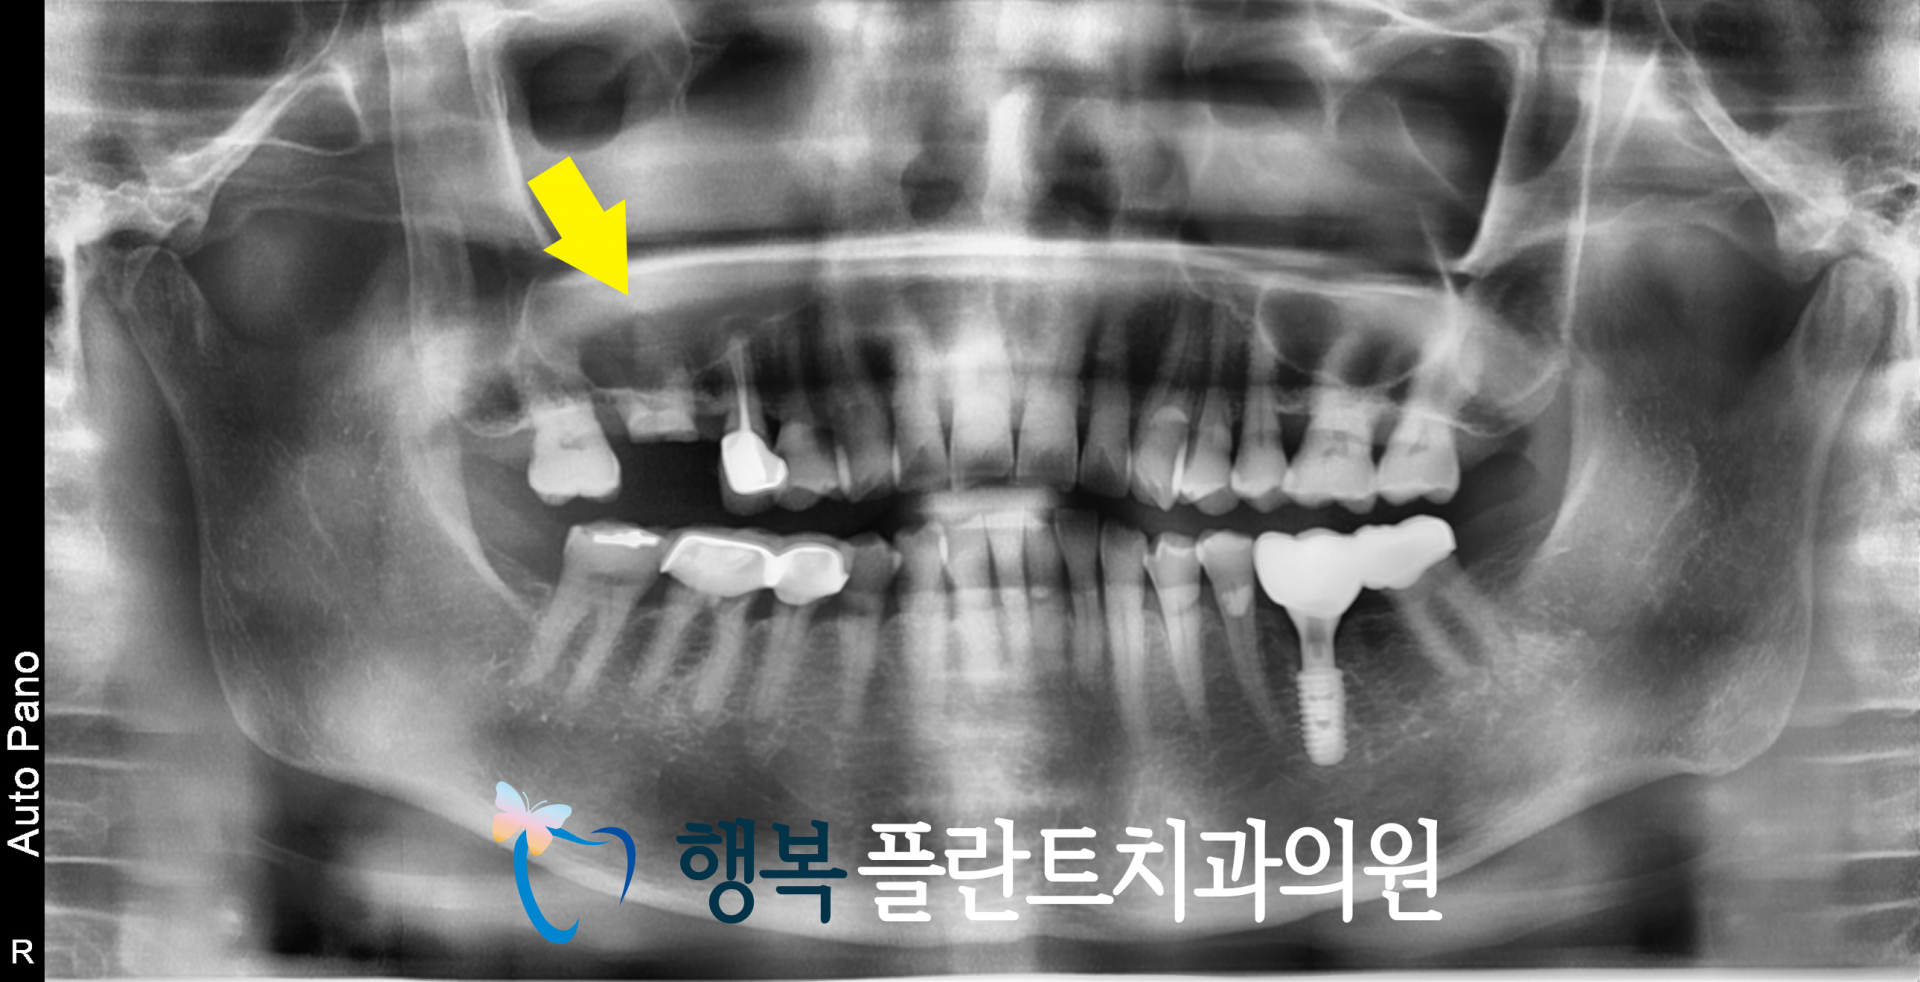

이번에 소개해 드릴 환자분은 치아머리 부분이 크게 파절되어 뿌리만 남아 있는 상태로 천안치과에 방문하셨습니다.

[심하게 부러져버린 치아머리]

엑스레이를 통해 보면 남아있는 잇몸뼈가 많지 않은 것을 확인할 수 있는데요.

이 경우엔 치아를 발치하게 되면 남아있는 잇몸뼈가 너무 부족하다 보니 임플란트를 심더라도 고정이 되지 않습니다.